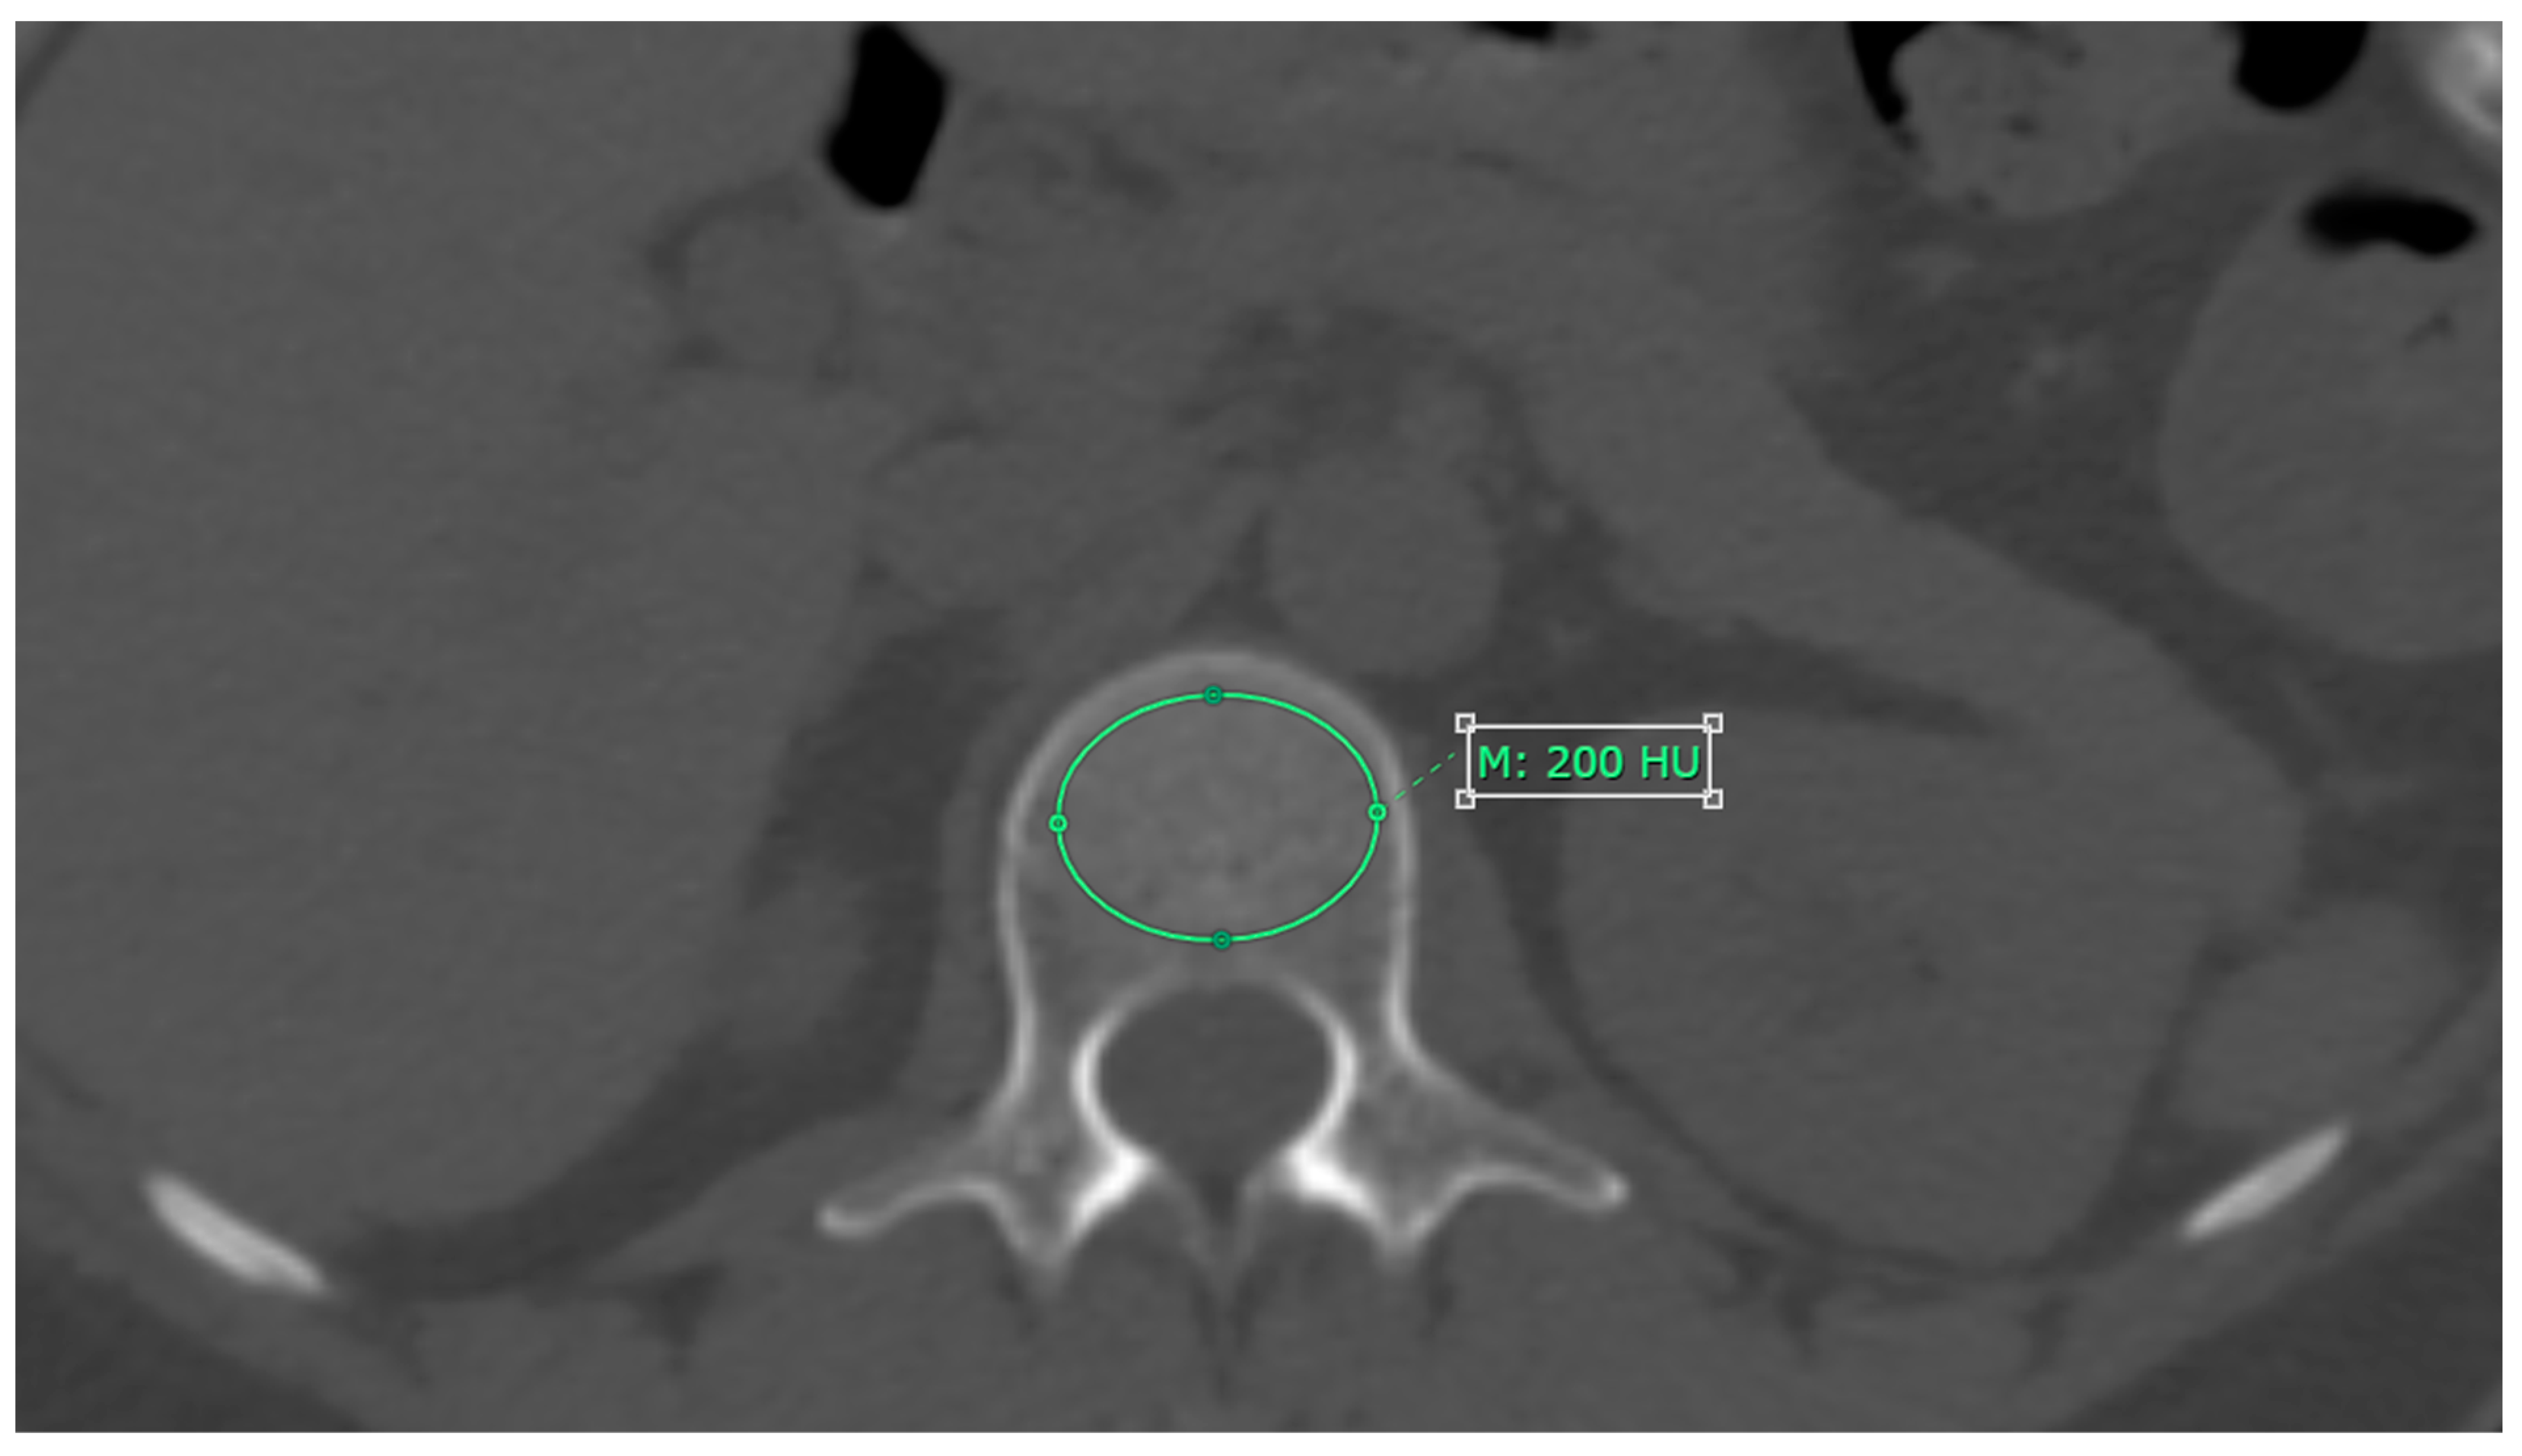

2.3. CT Attenuation Measurement

3.2. CT Attenuation Values